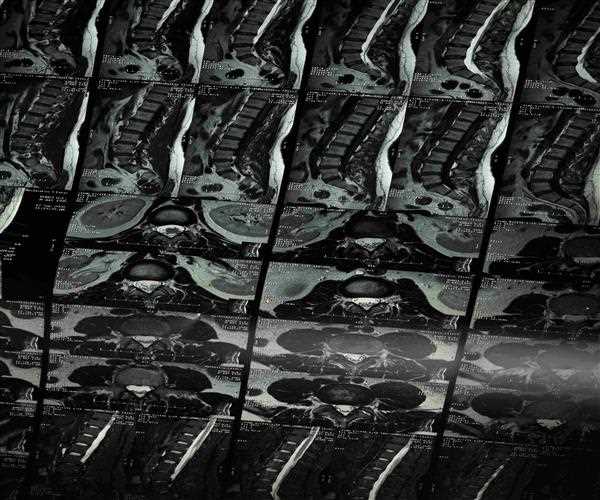

Scoliosis: Types, Causes and Prevention